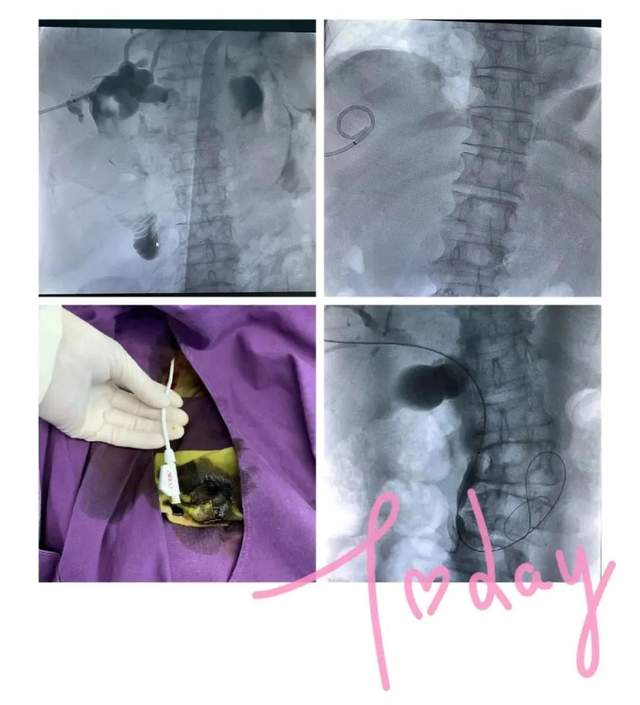

PTCD(经皮肝内胆管引流)

静脉输液港置入